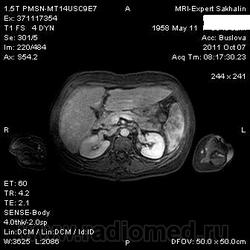

Изменения печени и селезенки.

Сегодня приходила женщина на исследование с жалобами на боли в подреберье, явления диспепсии.

похоже на метастазы, особенно в селезёнке, с центральным распадом. Хотелось бы и Т1 ВИ увидеть.Чётче на них видны были бы видны очаги в печени и вообще метастазы меланомы например могут иметь усиленный сигнал по Т1. а то в печени как будто множественные гипоинтенсивные очаги с отёком, но не совсем уверен, выглядит как просто пёстрая картинка.

а не лимфома это ? печень мне видится в  виде узлового поражения  и очаговое поражение селезенки.

Метастатическое поражение печени и селезенки, характерно для мелко-клеточного рака легкого.